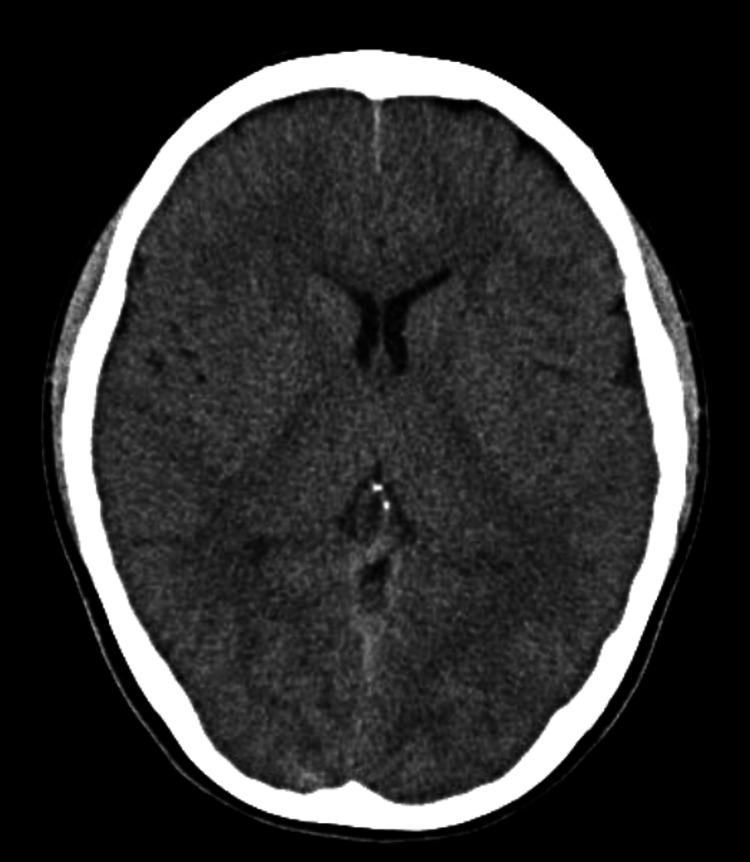

一名青春期女孩因原发性甲状旁腺功能减退症导致严重低钙血症和QT间期延长并伴有短暂意识丧失。

Transient Loss of Consciousness Associated With Severe Hypocalcemia and QT Prolongation Due to Primary Hypoparathyroidism in an Adolescent Girl.

As hypocalcemia is uncommon, serum calcium levels are not routinely measured in many emergency medicine clinics. We report a case of an adolescent girl with a transient loss of consciousness due to hypocalcemia. A 13-year-old healthy girl had a syncopal episode complicated with numbness in the extremities. On admission, she was fully conscious, but hypocalcemia and QT prolongation were noted. After careful consideration of the possible etiologies, the patient was diagnosed with acquired QT prolongation due to primary hypoparathyroidism. The patient's serum calcium levels were controlled by activated vitamin D and calcium supplementation. Primary hypoparathyroidism-associated hypocalcemia can cause QT prolongation and neurological complications, even in previously healthy adolescents.

摘要

由于低钙血症并不常见,许多急诊医学诊所并不常规检测血清钙水平。我们报告一例因低钙血症导致短暂意识丧失的青春期女孩病例。一名13岁健康女孩发生晕厥,伴有四肢麻木。入院时,她意识清醒,但发现有低钙血症和QT间期延长。在仔细考虑可能的病因后,患者被诊断为原发性甲状旁腺功能减退所致的获得性QT间期延长。通过活性维生素D和补钙控制患者的血清钙水平。原发性甲状旁腺功能减退相关的低钙血症即使在既往健康的青少年中也可导致QT间期延长和神经并发症。